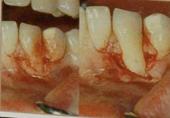

4.Bruno (1994) – модификация метода Langer и Langer без вертикальных разрезов, что улучшило эстетический результат и увеличило площадь кровоснабжения трансплантата. Разрез у сосочков проводится под прямым углом для плотного сопоставления и ушивания краев трансплантата и донорской раны «стык в стык». Трансплантат всегда помещается на надкостницу, поэтому ткани расщепляются на первичный лоскут и принимающее ложе. Для ушивания без натяжения проводится широкая препаровка в основании и по боковым краям первичного лоскута. Для надежной фиксации трансплантата используются позиционирующие (фиксация в нужном положении) и фиксирующие швы (удержание на принимающем ложе).